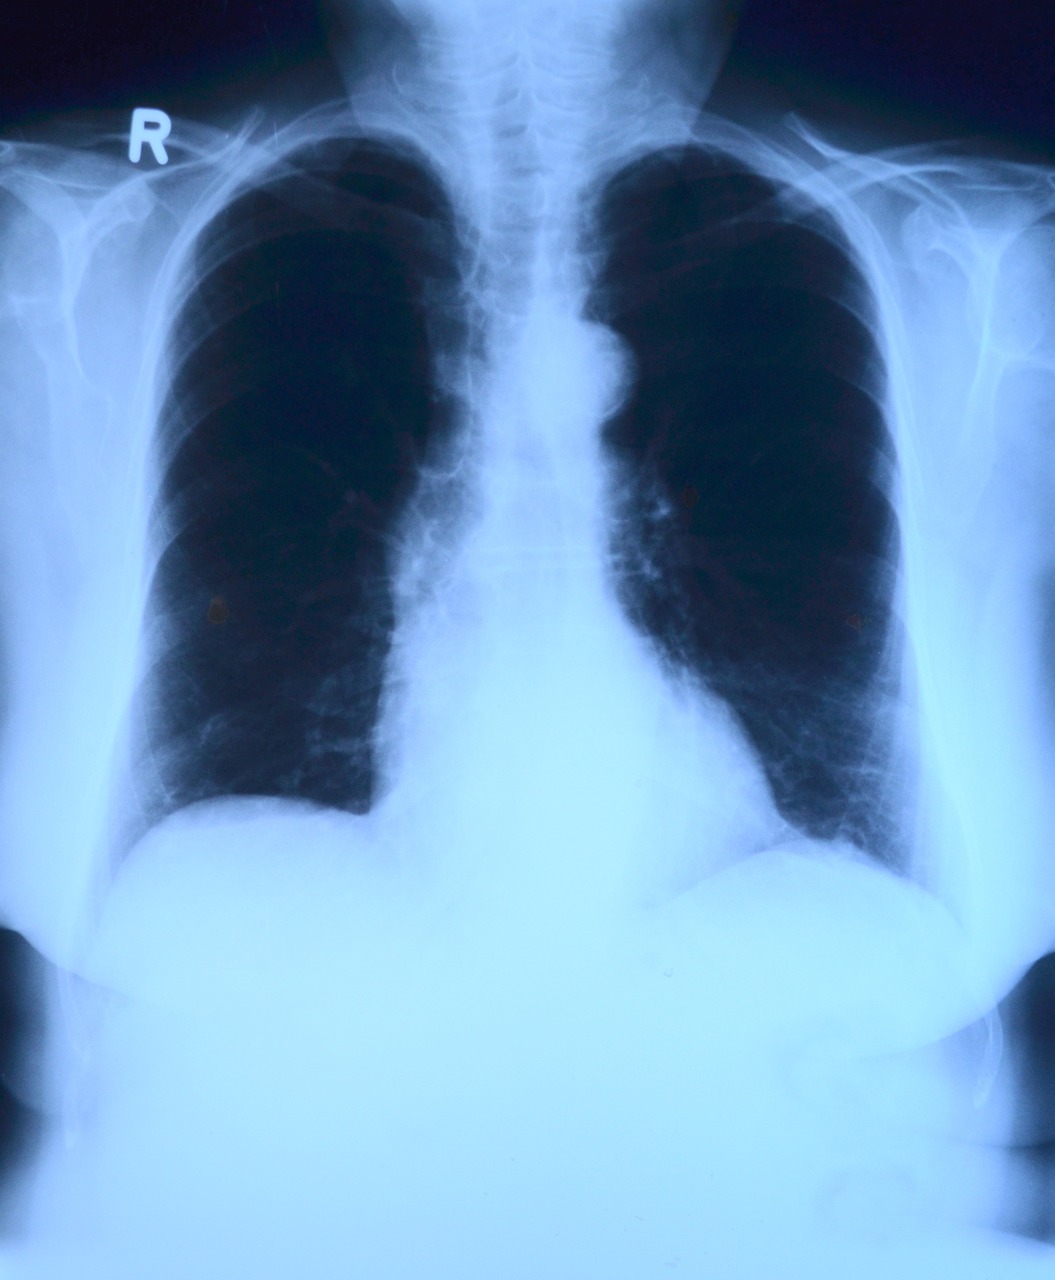

폐렴구균은 호흡기를 통해 전염되는 세균으로, 폐렴뿐 아니라 중이염, 부비동염, 패혈증, 뇌수막염 등 다양한 감염증의 원인이 된다. 그중에서도 폐렴은 고령층에게 가장 흔하게 발생하는 질환이며, 이는 입원과 사망으로 이어질 수 있어 결코 가볍게 볼 수 없다.

특히 65세 이상 노인, 심장병, 폐질환, 당뇨병 등 만성질환을 가진 사람, 흡연자, 면역저하자 등은 폐렴구균 감염에 취약하다. 국내 통계에 따르면 침습성 폐렴구균 감염증(IPD)의 치명률은 일반 폐렴보다 훨씬 높은 편이며, 고령자의 경우 감염 후 회복력이 떨어져 장기적인 후유증을 남길 수 있다.